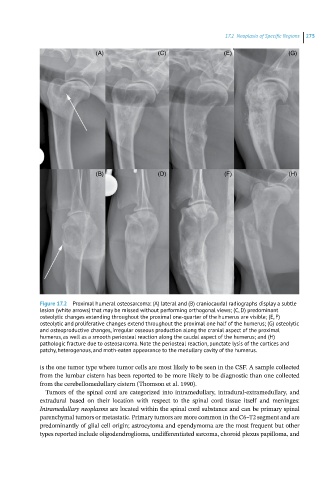

Figure 17.2 Proximal humeral osteosarcoma: (A) lateral and (B) craniocaudal radiographs display a subtle

lesion (white arrows) that may be missed without performing orthogonal views; (C, D) predominant

osteolytic changes extending throughout the proximal one‐quarter of the humerus are visible; (E, F)

osteolytic and proliferative changes extend throughout the proximal one half of the humerus; (G) osteolytic

and osteoproductive changes, irregular osseous production along the cranial aspect of the proximal

humerus, as well as a smooth periosteal reaction along the caudal aspect of the humerus; and (H)

pathologic fracture due to osteosarcoma. Note the periosteal reaction, punctate lysis of the cortices and

patchy, heterogenous, and moth‐eaten appearance to the medullary cavity of the humerus.